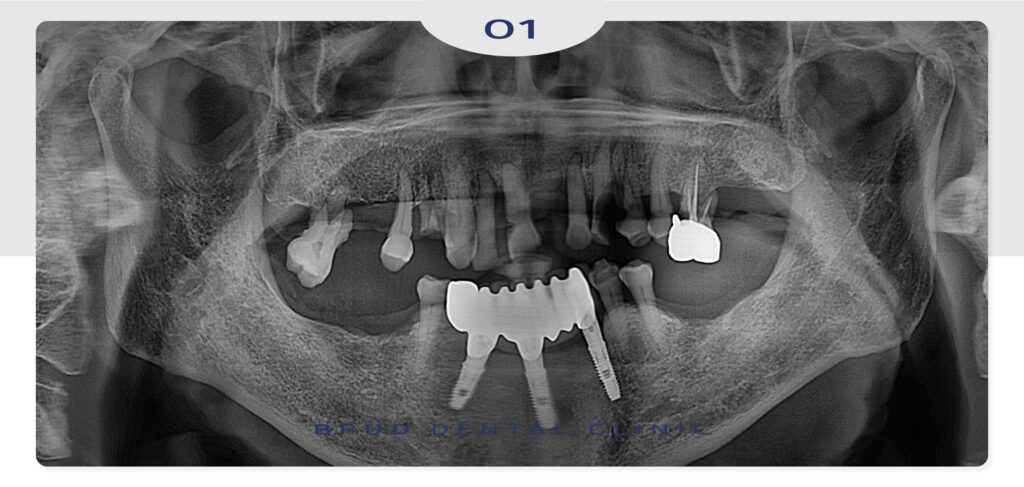

25.08.07

시간이 오래 걸리는 위쪽은 10개의

임플란트를 동시에 식립하고 아래쪽은

식립 후 최종 보철물을 먼저 마무리하였습니다.

수술은 치조골의 상태에 따라 1차로

임플란트를 식립하고 일정 기간 골융합

(뼈와 임플란트가 결합하는 과정)을 기다린 뒤,

보철물을 장착하는 순서로 진행되는데요.

환자분의 뼈가 단단하고 건강한 경우라면

즉시 임플란트를 통해 당일 식립이 가능할 수 있지만

반대로 치조골이 약한 경우에는 뼈이식이나

상악동 거상술 등의 보조적 치료가 필요할 수 있습니다.